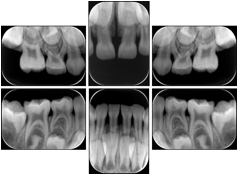

Intra-oral radiography typically involves acquisition of multiple images of various parts of the dentition. Many digital radiographic systems offer customized templates that are used for displaying the images in a study on the screen. These templates may also be referred to as mounts or view sets. The Structured Display Object represents a standard method of encoding and exchanging the layout and intended display of Structured Displays. A structured display object created in this manner could be stored with a study and exchanged with images to allow for complete reproduction of the original exam.

1. A patient visits a General Dentist where a Full Mouth Series Exam with 18 images is acquired. The dentist observes severe bone loss and refers the patient to a Periodontist. The 18 images from the Full Mouth Series along with a Structured Display are copied to a DICOM Interchange CD and sent with the patient to see the specialist. The Periodontist uses the CD to open the exam in his Dental Radiographic Software and consults via phone with the General Dentist. Both are able to observe the same exam showing the images on each user's display using the exact same layout.

Intra-oral Full Mouth Series Structured Display

Figure OO-1. Intra-oral Full Mouth Series Structured Display